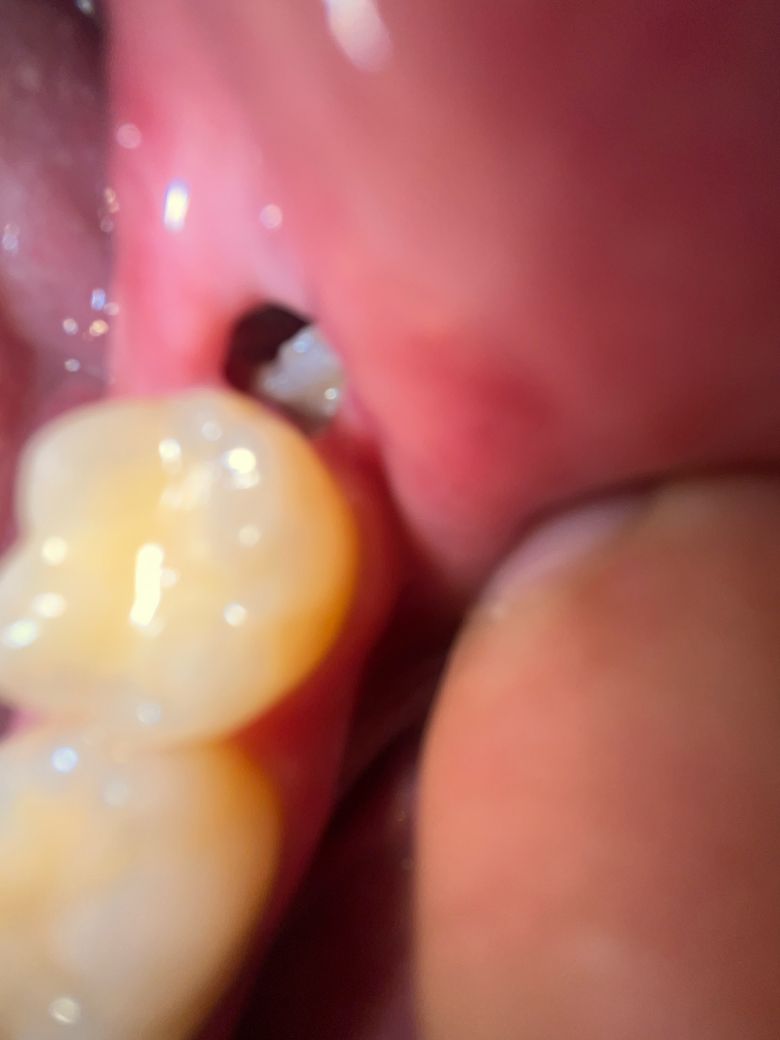

사랑니 발치 후 구멍에서 뼈 보이는 것 같습니다

발치를 한 지는 일주일이 좀 넘었습니다

오늘 발치 부위를 확인하는데 뼈같은 것이 보입니다

통증은 평상시엔 없고 건들면 좀 욱신거리는 정도입니다

음식물이 끼는 것 때문에 평소 가글과 주사기로 물쏘는 걸 조금 자주 하기는 했습니다

뼈가 맞을까요? 병원에 가는 것이 좋을까요?

• 1번 째 사진

뼈가 아니며 육아조직이거나 섬유화가 진행되고 있는 상태로 보여집니다. 물론 음식물이 약간 들어가 있는 부분이 있으나 이것은 큰 문제가 되지 않습니다. 초기에 혈병이 있다가 사라지면 보통 하얗게 변하게 됩니다. 현재 주변 잇몸 상태로 보아 정상적인 회복 과정입니다. 다만 물을 쏘거나 해당 부분을 너무 자극하지 않는 것이 좋습니다.

실제 뼈가 저정도로 드러난 상태면 치유 부전이고 상당한 통증이 있을겁니다. 뼈는 아니고 치유과정중에 생기는 부산물 같습니다. 너무 걱정안하셔도 되고 치과 굳이 안가보셔도 됩니다.